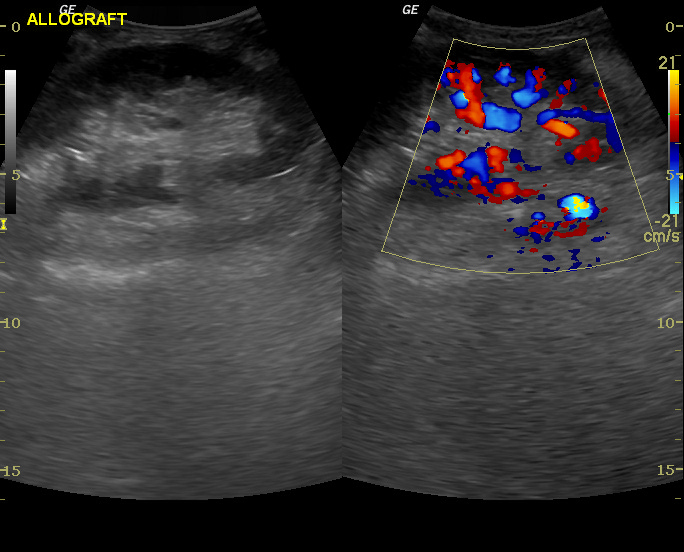

右圖:術後超音波顯示陳女士移植腎血流狀況良好。圖片提供/臺北慈濟醫院

前置性腎臟移植,先由泌尿科醫師執行腹腔鏡腎臟捐贈手術,再由游智欽醫師執行腎臟移植手術。術後陳女士恢復相當順遂,當天便排出尿液一萬c.c.,第二天轉出加護病房,肌酸酐降至1.2mg/dL,經免疫藥物調整,一個星期後順利出院。陳女士也放下心中憂慮感恩道:「因為有醫護人員的仔細衛教,讓我更有信心回歸未來生活!」